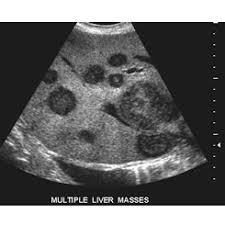

Any area that does not look like normal tissue is a possible cause for concern. In the table the differences in ultrasound appearances are listed. Needing a breast biopsy doesn't necessarily mean you have cancer. Ultrasound imaging is one of the most frequently used diagnosis tools to detect and classify abnormalities of the breast. Breast ultrasound is an imaging test that uses sound waves to look at the inside of your breasts.